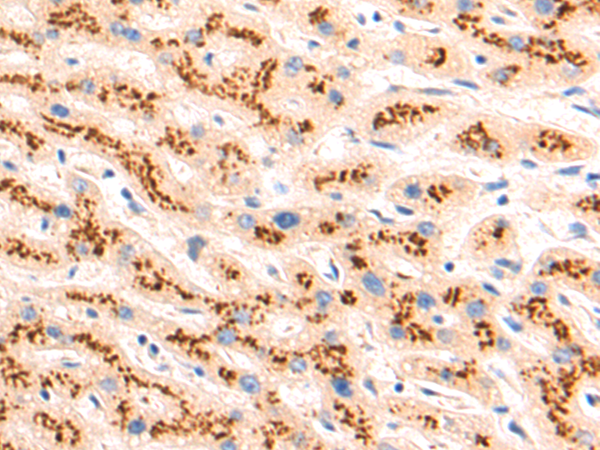

分类: 科研抗体货号: P09453别名: T3Z; CD3H; CD3Q; CD3Z; TCRZ; IMD25; CD3-ZETA应用: WB,IHC反应种属: Human, Mouse